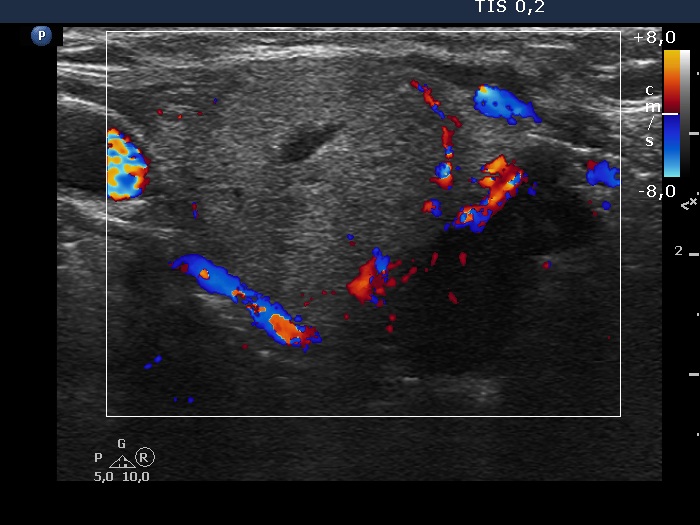

Right lobe, longitudinal scan

Right lobe, transverse view. The isoechoic lesion presents perinodular blood flow.